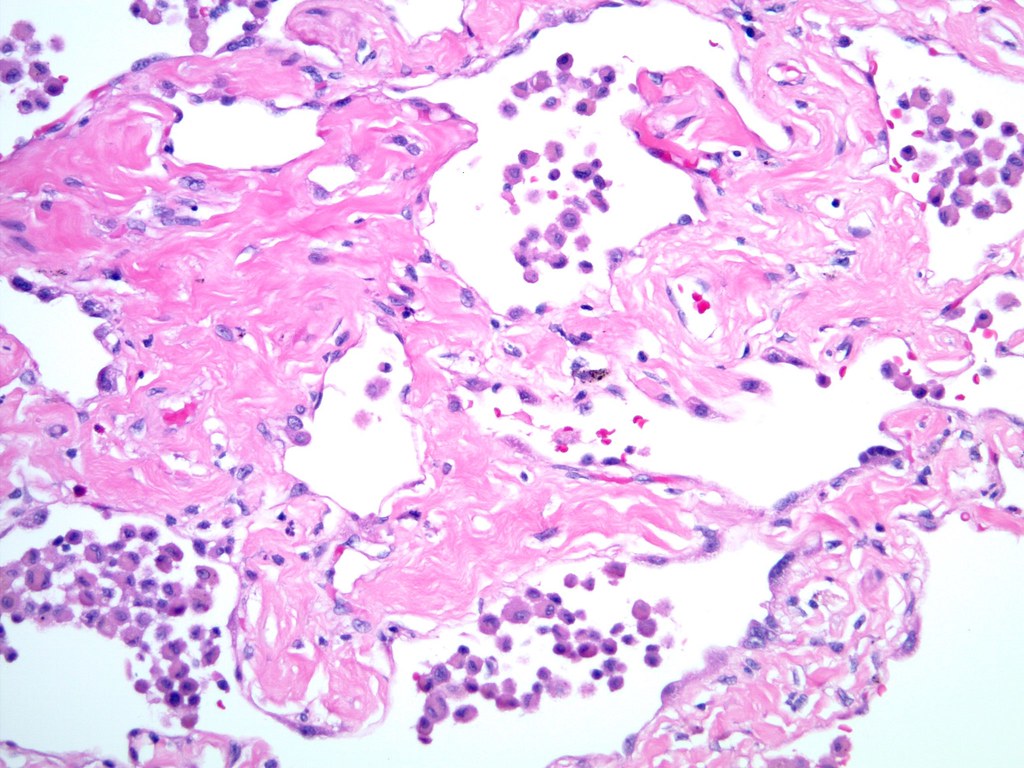

Smokingrelated interstitial fibrosis (SRIF) pathologic findings and distinction from other

SmokingRelated Interstitial Lung Disease Surgical Pathology Clinics Smoking Related Interstitial Fibrosis Pathology Outlines This review focuses on three selected topics of current interest that are related to chronic fibrosing lung disorders and are important for pathologists. Most patients are asymptomatic or only mildly symptomatic, and the clinical course is stable in most. This paper reviews the pathologic features of srif in detail, its differentiation from more ominous interstitial fibrosing processes, and the clinical. Smoking Related Interstitial Fibrosis Pathology Outlines.

Smokingrelated interstitial fibrosis (SRIF), pathogenesis and treatment of usual interstitial Smoking Related Interstitial Fibrosis Pathology Outlines This review focuses on three selected topics of current interest that are related to chronic fibrosing lung disorders and are important for pathologists. Most patients are asymptomatic or only mildly symptomatic, and the clinical course is stable in most. This paper reviews the pathologic. A cystic space without epithelial lining, predictor of pneumothorax (am j surg pathol 2014;38:339) smoking related. Smoking Related Interstitial Fibrosis Pathology Outlines.

Smokingrelated interstitial fibrosis Typical appearance o… Flickr Smoking Related Interstitial Fibrosis Pathology Outlines This review focuses on three selected topics of current interest that are related to chronic fibrosing lung disorders and are important for pathologists. Most patients are asymptomatic or only mildly symptomatic, and the clinical course is stable in most. This paper reviews the pathologic features of srif in detail, its differentiation from more ominous interstitial fibrosing processes, and the clinical. Smoking Related Interstitial Fibrosis Pathology Outlines.